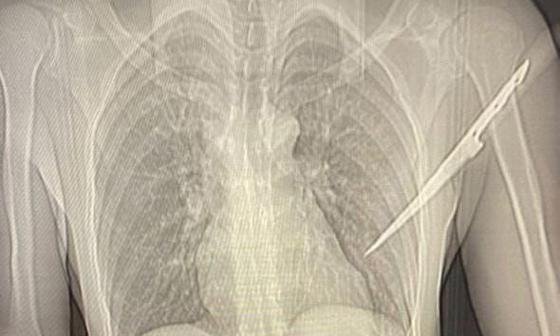

O homem, cujo nome não foi divulgado, recebeu atendimento médico urgente e precisou passar por uma cirurgia para a remoção da faca cravada em suas costas. Segundo informações médicas, seu estado de saúde é estável e ele não corre risco de vida.